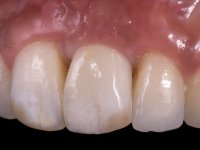

After 12 weeks the restorative procedure was initiated with a first impression to prepare a screw retained lab restoration. A temporary abutment for bone level implant was used to create a proper emergence profile. Two months after the placement, the peri-implant soft-tissue configuration was considered adequate to allow the final impression. In order to satisfy the high esthetic demands of the patient, the fixed rehabilitation was made with zirconium oxide abutment and a press lithium disilicate glass-ceramic restoration.

At the end of the treatment, a stable dental occlusion was accomplished. The midlines of both arches were aligned with facial midline and a correct overjet, overbite and bilateral Class I canine relationships were obtained. The rehabilitation of the left maxillary central incisor loss was accomplished with an implant and a ceramic crown placed after the proper alignment of the adjacent incisor teeth, rendering a complete anterior dentition and a nice smile.